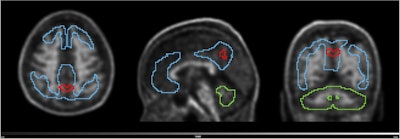

PET scans identify people at early risk for cognitive decline. Image from Guilherme Kolinger, MD, of Life Molecular Imaging in Germany, et al.

The second finalist for Best Radiology Image comes from a study reporting that amyloid PET scans in individuals with early signs of Alzheimer’s disease can identify those at higher risk of cognitive decline.

Image available for republishing under Creative Commons license (CC BY 4.0 DEED, Attribution 4.0 International) and courtesy of the European Journal of Nuclear Medicine and Molecular Imaging.

Image available for republishing under Creative Commons license (CC BY 4.0 DEED, Attribution 4.0 International) and courtesy of the European Journal of Nuclear Medicine and Molecular Imaging.

The study was conducted by scientists at Lantheus subsidiary Life Molecular Imaging, with the image demonstrating how quantitative analysis can reveal additional insights beyond standard visual assessment in amyloid PET.

“To identify the region highlighted in red, an amyloid-negative population (at baseline) with subjective cognitive decline was assessed with a voxel-based analysis using standardized uptake value ratios (SUVRs). Then, the baseline SUVR images of amyloid accumulators versus nonaccumulators were compared. Amyloid accumulation status was defined using the Centiloid method and with a five-year follow-up,” lead author Guilherme Kolinger, MD, explained to AuntMinnie.

The results showed that accumulators exhibited higher baseline SUVR in the red-marked region, which corresponds to part of the precuneus, a brain area known to play a role in early Alzheimer’s disease. This region overlaps with the Centiloid target region (shown in blue), underscoring the potential of this approach to enhance preclinical Alzheimer’s disease assessment, Kolinger added.